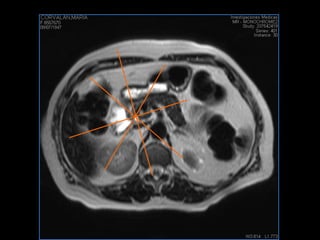

PROTOCOLO abdomen COR T2, AXIAL supresion grasa AX T1 +SAG T2  CON   GADOLINIO :  COR T1+AX T1(DIN) SAT: NO  FASE: RL THK: 6MM  COIL:  GAP: (FACTOR 1.4) 2MM FOV: 40 CM NEX:2 SINCRONIZACION RESPIRATORIA EN 3 O 4 CICLOS ALE